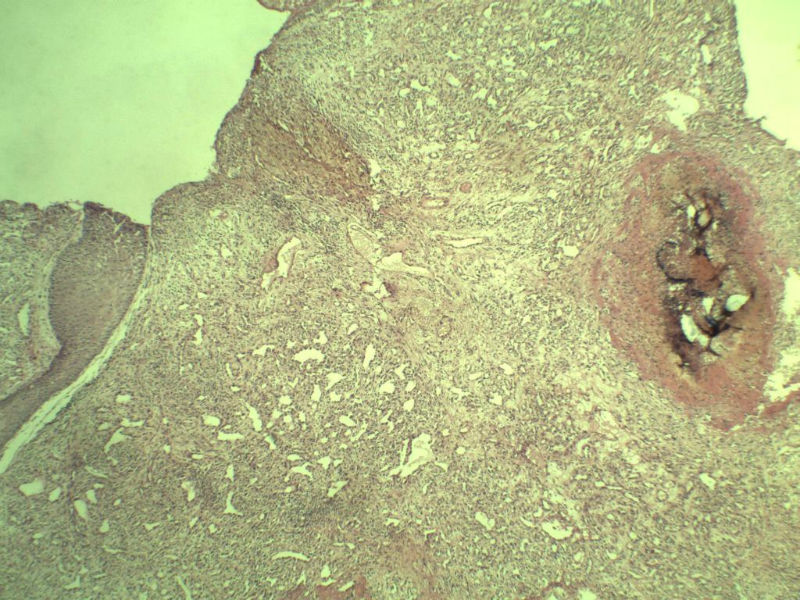

男 33岁 右手食指赘生物5个月 破溃流血一周 灰红不整形组织一块,体积 0.8 × 0.6 × 0.5 cm3。切面灰红,实性,质中。请各位老师看看 是什么? 谢谢了!